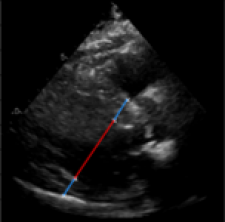

Left Ventricular Hypertrophy (LVH), one of the leading predictors of adverse cardiovascular outcomes, is the condition where heart’s mass abnormally increases secondary to anatomical changes in the Left Ventricle (LV) [10]. These anatomical changes include an increase in the septal and LV wall thickness, and the enlargement of the LV chamber. More specifically, Inter-Ventricular Septal (IVS), LV Posterior Wall (LVPW) and LV Internal Diameter (LVID) are assessed to investigate LVH and the risk of heart failure [21]. As shown in Figure 1 (a), four landmarks on a parasternal long axis (PLAX) echo frame can characterize IVS, LVPW and LVID, and allow cardiac function assessment. To automate this, machine learning-based (ML) landmark detection methods have gained traction.

It is difficult for such ML models to achieve high accuracy due to the sparsity of positive training signals (four or six) pertaining to the correct pixel locations. In an attempt to address this, previous works use 2D Gaussian distributions to smooth the ground truth landmarks of the LV [9, 13, 18]. However, as shown in Figure 1 (b), for LV landmark detection where landmarks are located at the wall boundaries (as illustrated by the dashed line), we argue that an isotropic Gaussian label smoothing approach confuses the model by being agnostic to the structural information of the echo frame and penalizing the model similarly whether the predictions are perpendicular or along the LV walls.